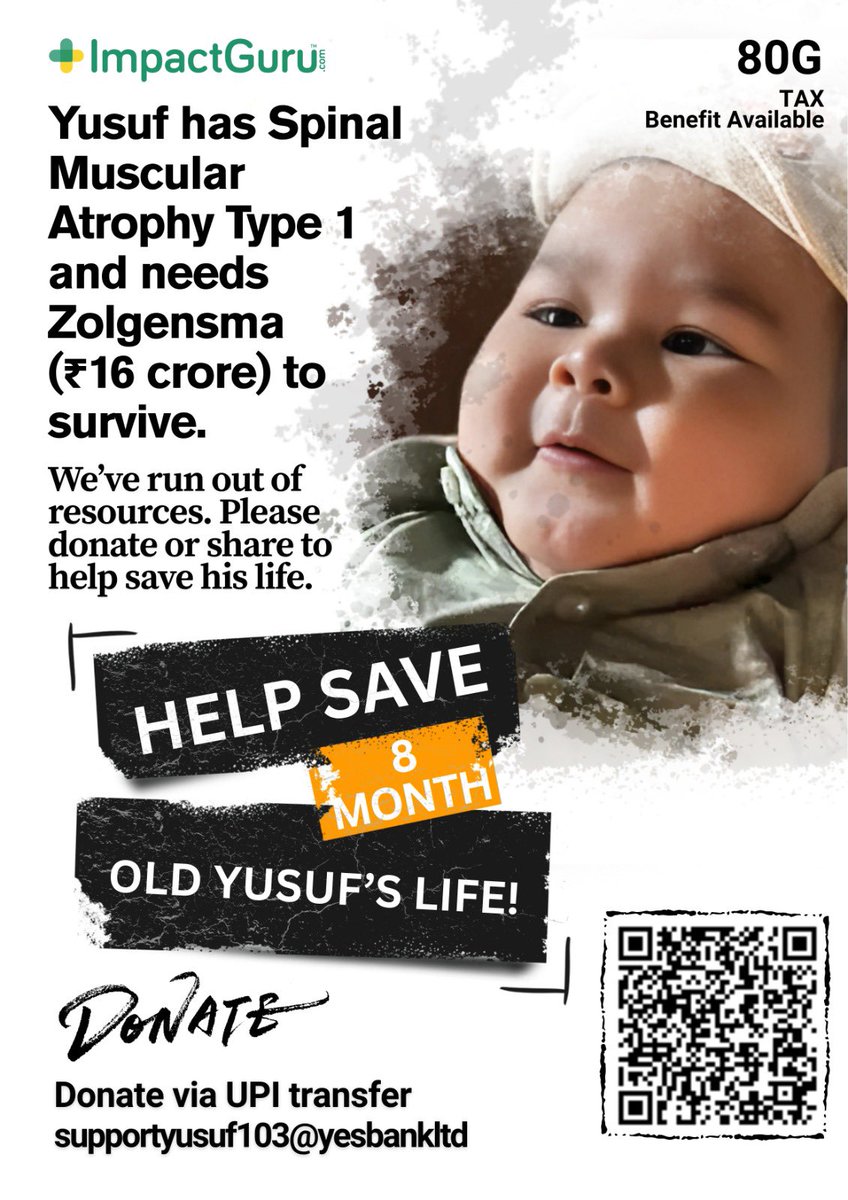

Urgency & Hope ⏳ Time is running out for Yusuf. SMA Type 1 worsens every single day. We are desperately seeking help to fund his treatment. Please join us in this fight for his life 🙏 Donate here: impactguru.com/fundraiser/hel… #SaveYusuf #DonateForYusuf @therantinggola @dhruv_rathee

Baby Yusuf deserves a chance to live, smile & grow like every child. But SMA Type 1 is stealing his childhood. Your support can give him life. Please donate & share 💙 👉 impactguru.com/fundraiser/hel… #SMAAwareness #SaveYusuf #zolgensma @BeingSalmanKhan @iamsrk @SonuSood @IrfanPathan

🙏This Ganesh Chaturthi, please be my baby’s Vighnaharta and help remove the biggest obstacle of his life SMA Type 1.💔 Celebrate this Ganesh Chaturthi by saving a baby’s life. Please donate & RT. 🔗 impactguru.com/fundraiser/hel… #SaveYusuf #GaneshChaturthi #SMA @SrBachchan @SonuSood

My 8month-old baby Yusuf is fighting a deadly disease SMA Type1. He needs ₹16Cr for a one-time cure—Zolgensma. We are begging for help.Every share, every rupee counts.🙏 👉impactguru.com/fundraiser/hel… #SaveYusuf #SMA #DonateForYusuf #Zolgensma #HelpSaveYusuf @tarak9999 @dhruv_rathee

Yusuf’s tiny heart is full of dreams, but SMA is stealing his time. ⏳ Please help us fight for his life. Please donate & share 🙏 💖 Donate here: impactguru.com/fundraiser/hel… #SaveYusuf #Donation #SMA @dhruv_rathee @TheJohnAbraham @timesofindia @TheShilpaShetty @BeingSalmanKhan

⏳ Time is running out! My baby Yusuf (11 months) is battling SMA Type 1 💔 Only your support can save his life. Please donate & share 🙏 Donate here :- impactguru.com/fundraiser/hel… #SaveYusuf #Donate #SMA @curesmaindia @therantinggola @iamsrk @akshaykumar @SrBachchan @CMOMaharashtra

⏳ Time is running out! My baby Yusuf (11 months) is battling SMA Type 1 💔 Only your support can save his life. Please donate & share 🙏 Donate here :- impactguru.com/fundraiser/hel… #SaveYusuf #Donate #SMA @curesmaindia @therantinggola @iamsrk @akshaykumar @SrBachchan @CMOMaharashtra

🙏This Ganesh Chaturthi, please be my baby’s Vighnaharta and help remove the biggest obstacle of his life SMA Type 1.💔 Celebrate this Ganesh Chaturthi by saving a baby’s life. Please donate & RT. 🔗 impactguru.com/fundraiser/hel… #SaveYusuf #GaneshChaturthi #SMA @SrBachchan @SonuSood

Urgency & Hope ⏳ Time is running out for Yusuf. SMA Type 1 worsens every single day. We are desperately seeking help to fund his treatment. Please join us in this fight for his life 🙏 Donate here: impactguru.com/fundraiser/hel… #SaveYusuf #DonateForYusuf @therantinggola @dhruv_rathee

Baby Yusuf deserves a chance to live, smile & grow like every child. But SMA Type 1 is stealing his childhood. Your support can give him life. Please donate & share 💙 👉 impactguru.com/fundraiser/hel… #SMAAwareness #SaveYusuf #zolgensma @BeingSalmanKhan @iamsrk @SonuSood @IrfanPathan